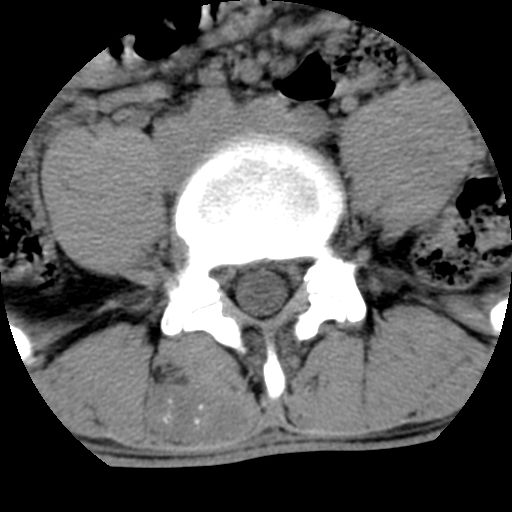

男,腰背痛

本人诊断1tb2包虫,请会诊

1)右侧竖脊肌稍低密度肿块伴钙化(性质待定),不排除肿瘤可能;建议行进一步检查。2)腰椎间盘突出。

考神经源性肿瘤可能性,不除外结核,建议增强.椎间盘突出

1.右侧竖脊肌软组织肿块伴团块状钙化,首先考虑血管瘤可能性大;建议行进一步检查;2。腰椎间盘突出。

软骨肉瘤可能性大